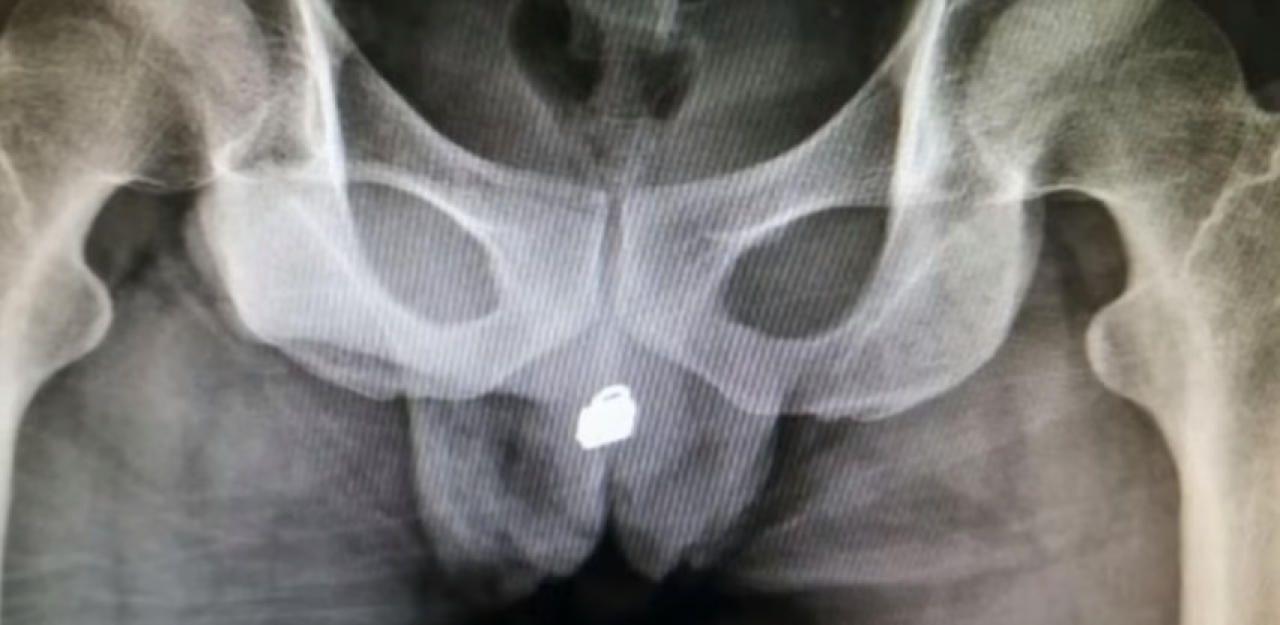

Hier das unglaubliche Röntgenbild.